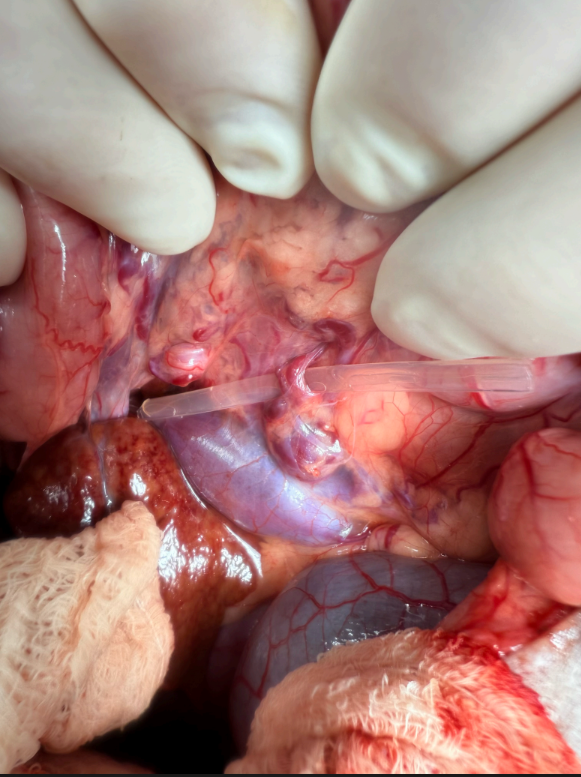

- The gallbladder was of normal color, soft, mildly to moderately dilated, but normally expressible. The cystic duct and common bile ducts were both moderately dilated without evidence of obstruction. Intrahepatic biliary ducts were not able to be visualized. - After continued exploratory, the anomalous shunting vessel was identified; it was extremely short and markedly tortuous, forming multiple acute angles on itself. The tortuous vessel was noted to originating from dorsal and deep to the stomach, coursing deep to the pancreatic and splenic vasculature, before entering the Caudal Vena Cava immediately cranial and adjacent to the left renal vein. A mild amount of turbulent flow was noted within the Caudal Vena Cava, near the point of entry of the anomalous vessel. No additional abnormalities noted during exploratory.

- Cellophane band was passed around the vessel, routinely secured with multiple alternating metallic hemoclips (3 in total). No immediate signs of intraoperative portal hypertension were noted. A guillotine biopsy was taken from the caudodorsal margin of the quadrate liver lobe.

Image shows intra-operative view of intact vascular anomaly, labeled to provide a framework for the tortuous vessel. EHPSS (extra hepatic portosystemic shunt)

Image of the isolates shunted vessel prior to being ligated.